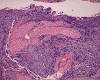

The surgery removed several irregular fragments of tan, soft tissue for examination that were 2.5 x 1.2 x 1.0 cm in toto. Histologically, the lesion is a highly cellular neoplasm with tumor cells packed in solid sheets and without a specific architectural pattern (Panel D). Small, focal necrosis is also present (not shown). The tumor has rich vascularity and the endothelial cells seem to be active (Panel E). Almost all the tumor cells have only a thin rim of amphophilic cytoplasm, large nuclei with prominent nucleoli (Panel E and F). Clear cytoplasm is present in some tumor cells. In general, the cells do not look epithelioid or spindle. In some of the tissue fragment, the tumor shows invasion into the peripheral nerve root with dissection of the nerve fibers (Ú in Panel G and H). This phenomenon is well demonstrated by reticulin stain (Panel I) and immunohistochemistry for neurofilament proteins (Panel J). About half of the tumor cells are strongly positive for vimentin (Panel K). There is also scant positive tumor cells for S100 protein (Panel L) and cytokeratin AE1/3 (Panel M). The tumor cells are negative for neuorfilament proteins (Panel K) and smooth muscle protein (Panel N).

The tumor under discussion is undifferentiated or poorly differentiated. The scant positive cells for S100 protein cannot strongly support a schwann cell origin. The lack of expression of EMA does not support a peirneurial or meningothelial origin. Therefore, these results do not suppoart a diagnosis of malignant peripheral nerve sheath tumor (MPNST) or meningioma. Both entities are unusual in this age group. While many MPNST may express cytokeratin AE1/AE3, the expression of a scant amount of cytokeratin does not totally rule out the possibility of a MPNST. Although the peripheral nerve bundles are diffusely infiltrated by the tumor as shown in Panel G and H and may suggest a malignant tumor arising from a nerve trunk, there is a lack of solid evidence to prove that this tumor is arising from a nerve trunk. Although a MPNST is suspected, the age and location is quite usual for this entity. The tumor under discussion is best classified as an undifferentiated sarcoma.